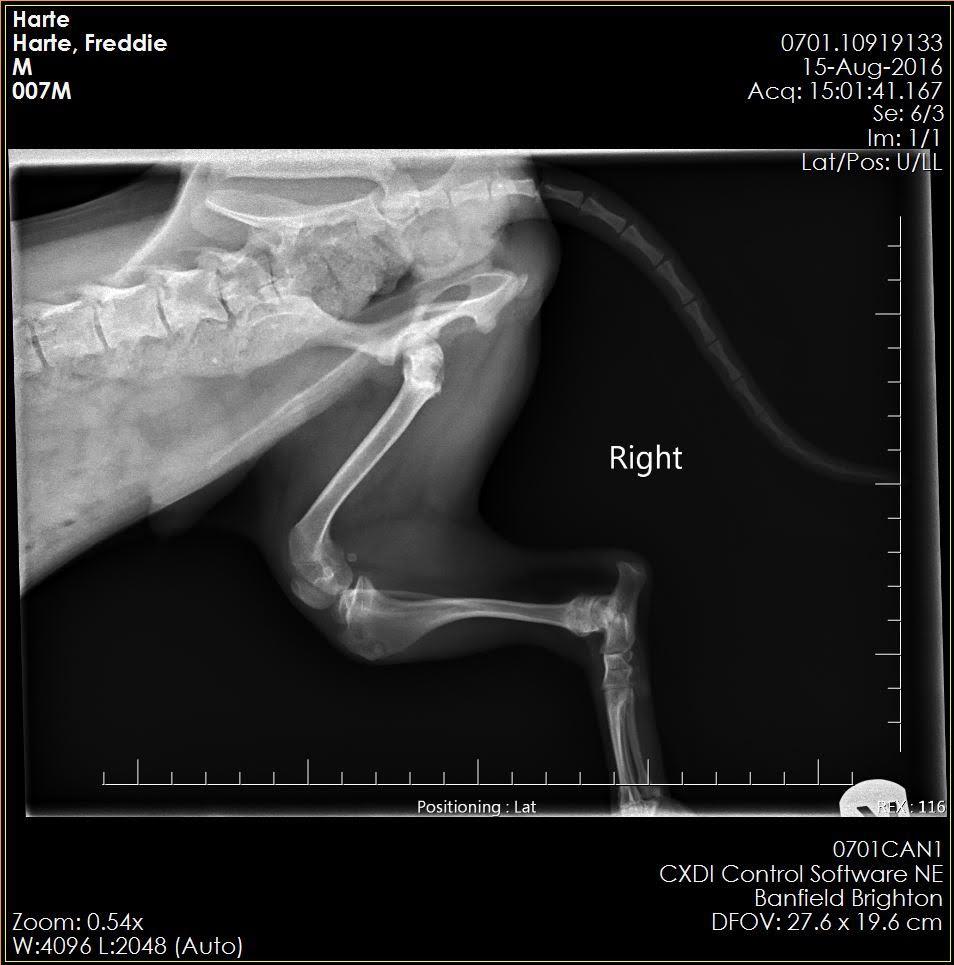

these are X-rays of my 1.5-year-old Yorkie Shih Tzu Mix or a Shorkie-Zu, his name is Freddie. He sometimes limps but mostly he doesn’t. He has as you can see muscle built up on his left leg. It seems like he limps on both of them when he does but he doesn't do it consistently. He had a cryptic orchid that has been removed. I have been told they don't know what is wrong with him.

I'm sorry to hear about Freddie Harte's limping. I am not seeing any obvious defects on this x-ray. The challenge is that the findings on exam are extremely important in trying to diagnose orthopedic issues; it would help to know if Freddie has proprioceptive deficits in his hind end, decreased range of motion, muscle atrophy, medial buttressing, etc as well as trying to localize any pain that may be contributing to his limping - all of this information would be combined with findings on x-ray to try to reach a diagnosis. Small dogs such as Shih Tzus are prone to luxating patellas, which may not always be evident on an x-ray but would be detected on exam. Did your vet discuss the option of referral to a specialist for a more concrete answer? I'm happy to give you my input on the x-ray - but referral to an orthopedic specialist who will be able to put their hands on your dog, as well as look at these x-rays, will give you much more beneficial input. I know its frustrating to have a chronically limping dog without an answer! I hope this helps!